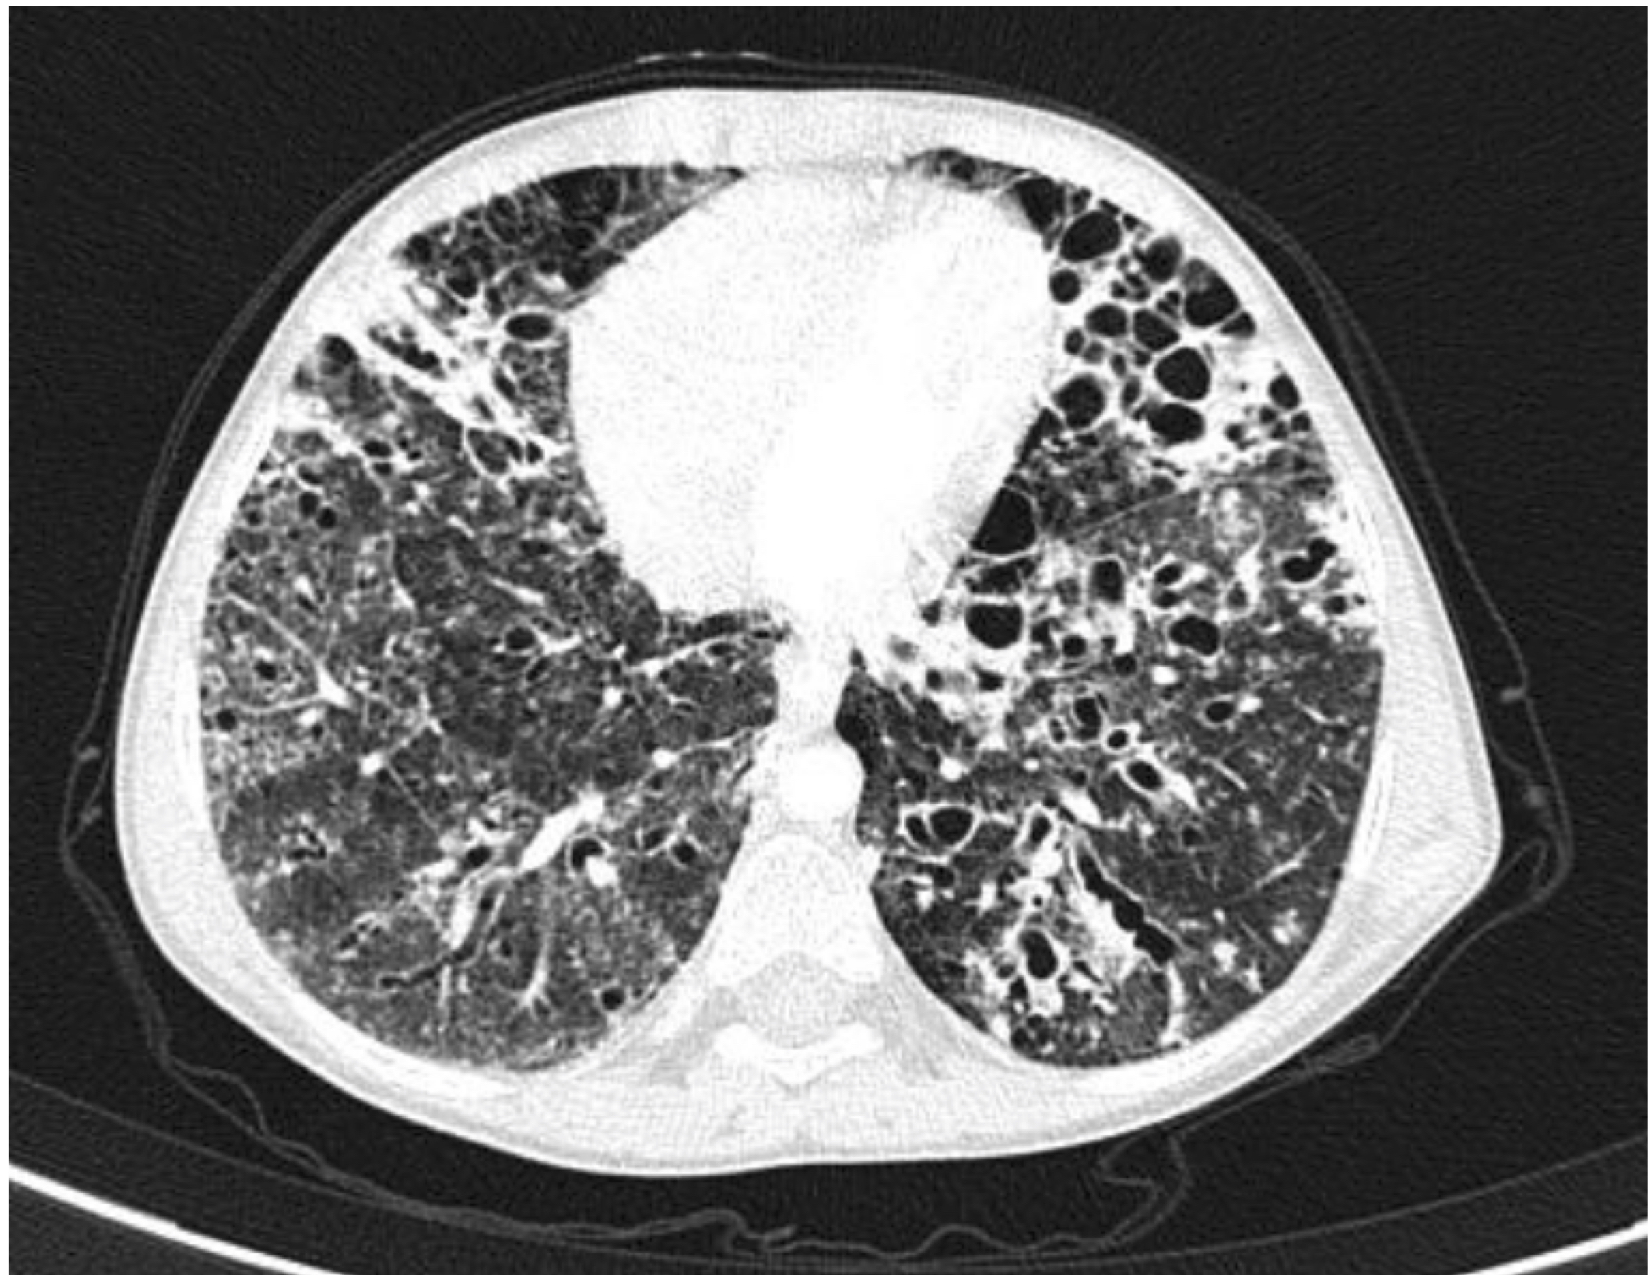

Ground-glass opacity diffusely distributed in both lungs with multiple bronchiectasis involving predominantly lung bases. Cystic images diffusely distributed in both lungs, some subpleural and other centrilobular.